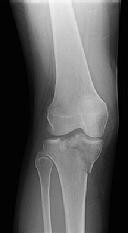

Figures 1 through 3 are the radiographs of a 25-year-old man who is brought to the emergency department after a motorcycle collision. He is complaining of isolated knee pain. Examination reveals swelling, popliteal ecchymosis, joint line pain, and limited knee joint motion. His pulses and sensation are normal.

This knee injury is best described as a